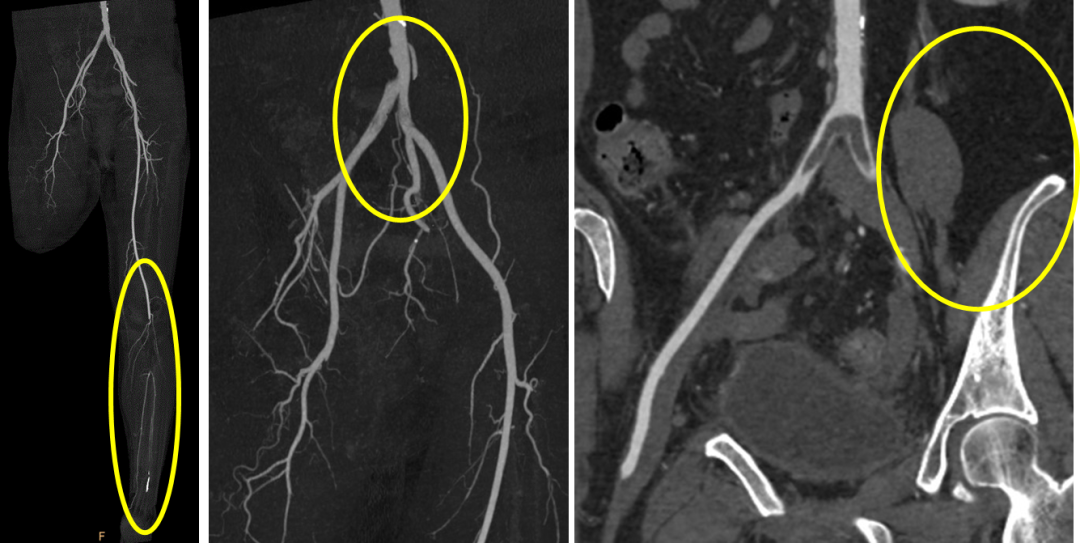

术前CTA

术前诊断

血栓闭塞性脉管炎

右下肢动脉血栓形成

2型糖尿病(新)

高血压病